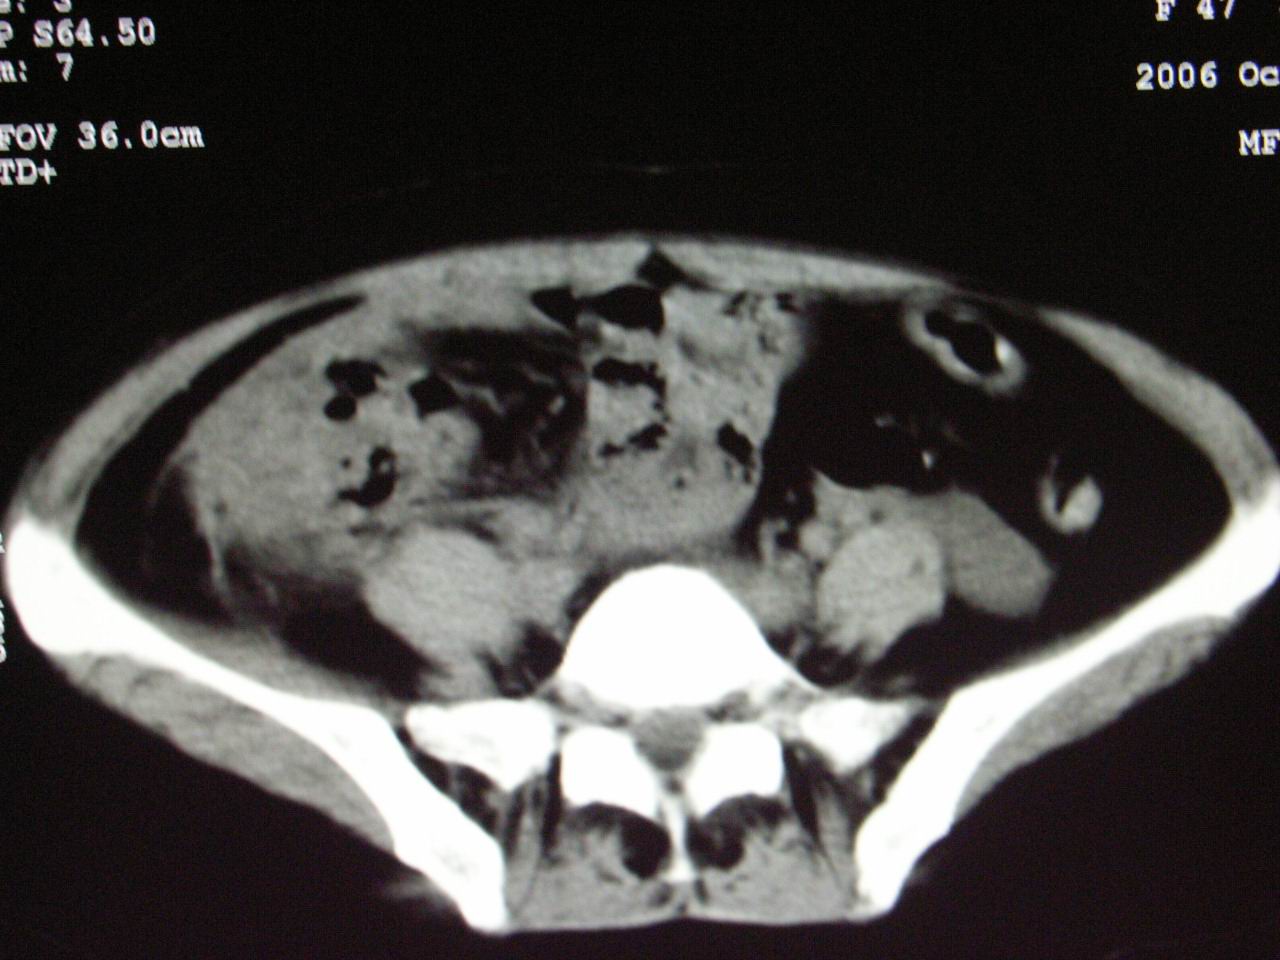

男;67岁,腹胀,腹痛,便血半年;钡餐透视发现右下腹部占位性病变

ct表现;病灶成环状软组织肿块,表现为不对称的肠壁增厚;肠腔变型.

升结肠ca。

升结肠肠壁不均匀增厚,肠腔变形,支持结肠癌.